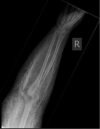

Methods: Two cases were compared in the context of the prevailing literature. One of these was a large volume extravasation of an iodine-based imaging contrast agent with a diffuse distribution pattern, rendering it unsuitable for this method of evacuation. This is contrasted with a case with a more discrete collection better suited to acute evacuation.